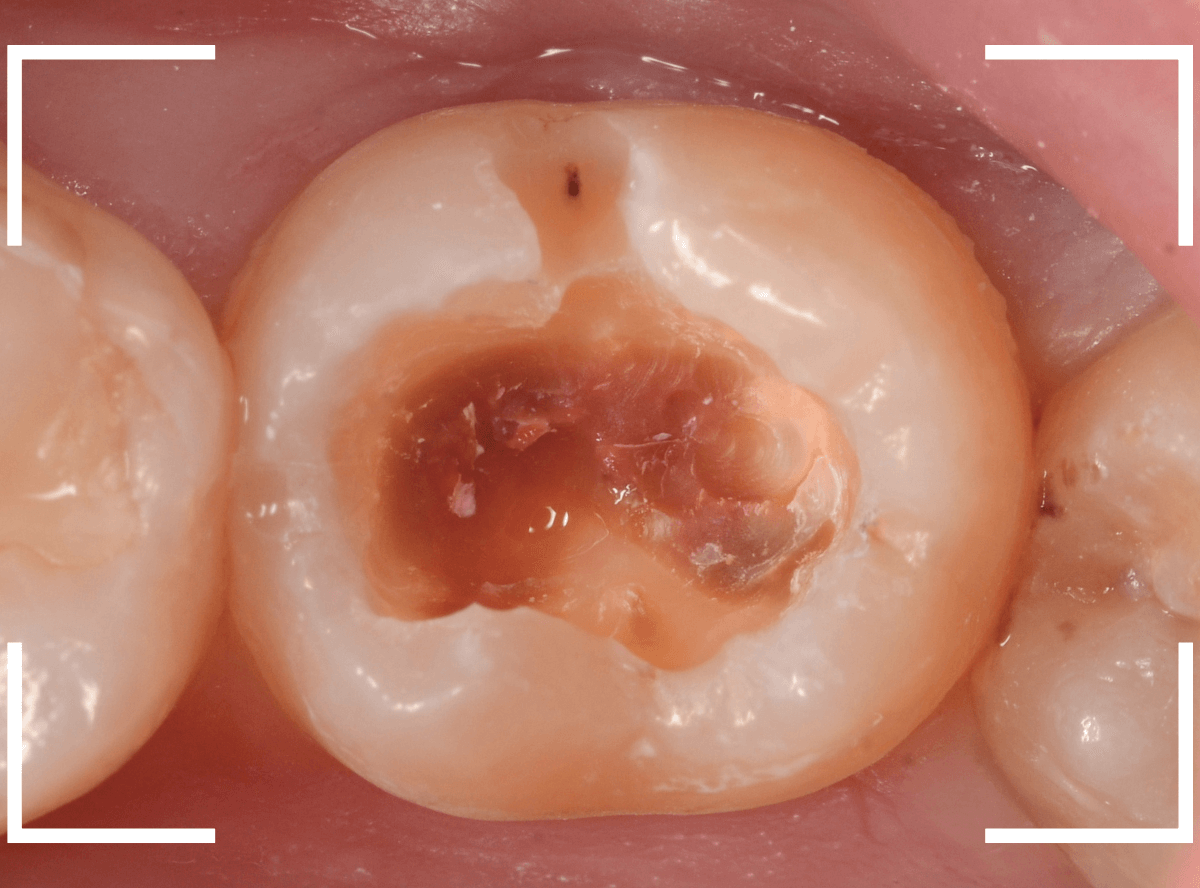

Case.15 下の奥歯がたまに痛い

メンテナンス中に、「下の奥歯がたまに痛い」という訴えをされた患者さんです。

「奥歯がたまに痛いけど、どの歯かははっきりわからない」という事で、Case.15のように、打診をしてもどの歯も特に反応もありませんでしたが、レジンの中の虫歯が怪しい歯がありました。

レントゲン写真で確認します。

あまりはっきりしませんが、レジンの下で虫歯がありそうな感じです。

レジンを外して中を調べます。

それほど深くはありませんでしたが、レジンの中で虫歯が進行しはじめていました。

全ての虫歯を除去したところです。

レジンをつめ直して治療終了です。

おそらくこれで症状は改善されるでしょう。

「たまに痛い」など、症状がハッキリしない場合は、原因も見つけづらい事が多いです。

今回は、レントゲン写真から原因が推察できましたので、良かったです。